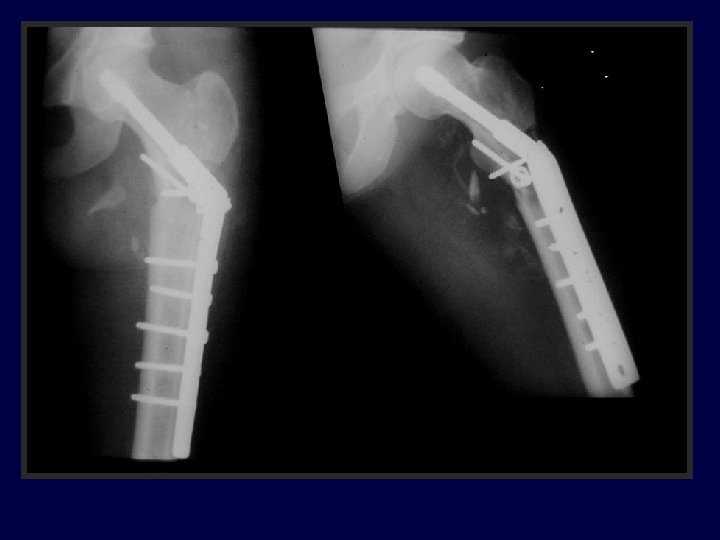

27 yo jogger struck by car, closed, isolated injury

27 yo jogger struck by car I’d reduce & fix with: A. 95° blade B. DCS plate C. “Recon” Nail D. DHS E. Intramedullary hip screw (PFN, TFN, IMHS, GAMMA)

A. The reduction is satisfactory B. The TAD is satisfactory C. Both are satisfactory D. Neither are satisfactory

* *

Progressive pain 11 -14 weeks (varus + plate is rarely good)

I’d Bonegraft & revise with: A. 95° blade B. DCS plate C. “Recon” Nail D. DHS E. IMHS F Other

95° DCS + auto. BG